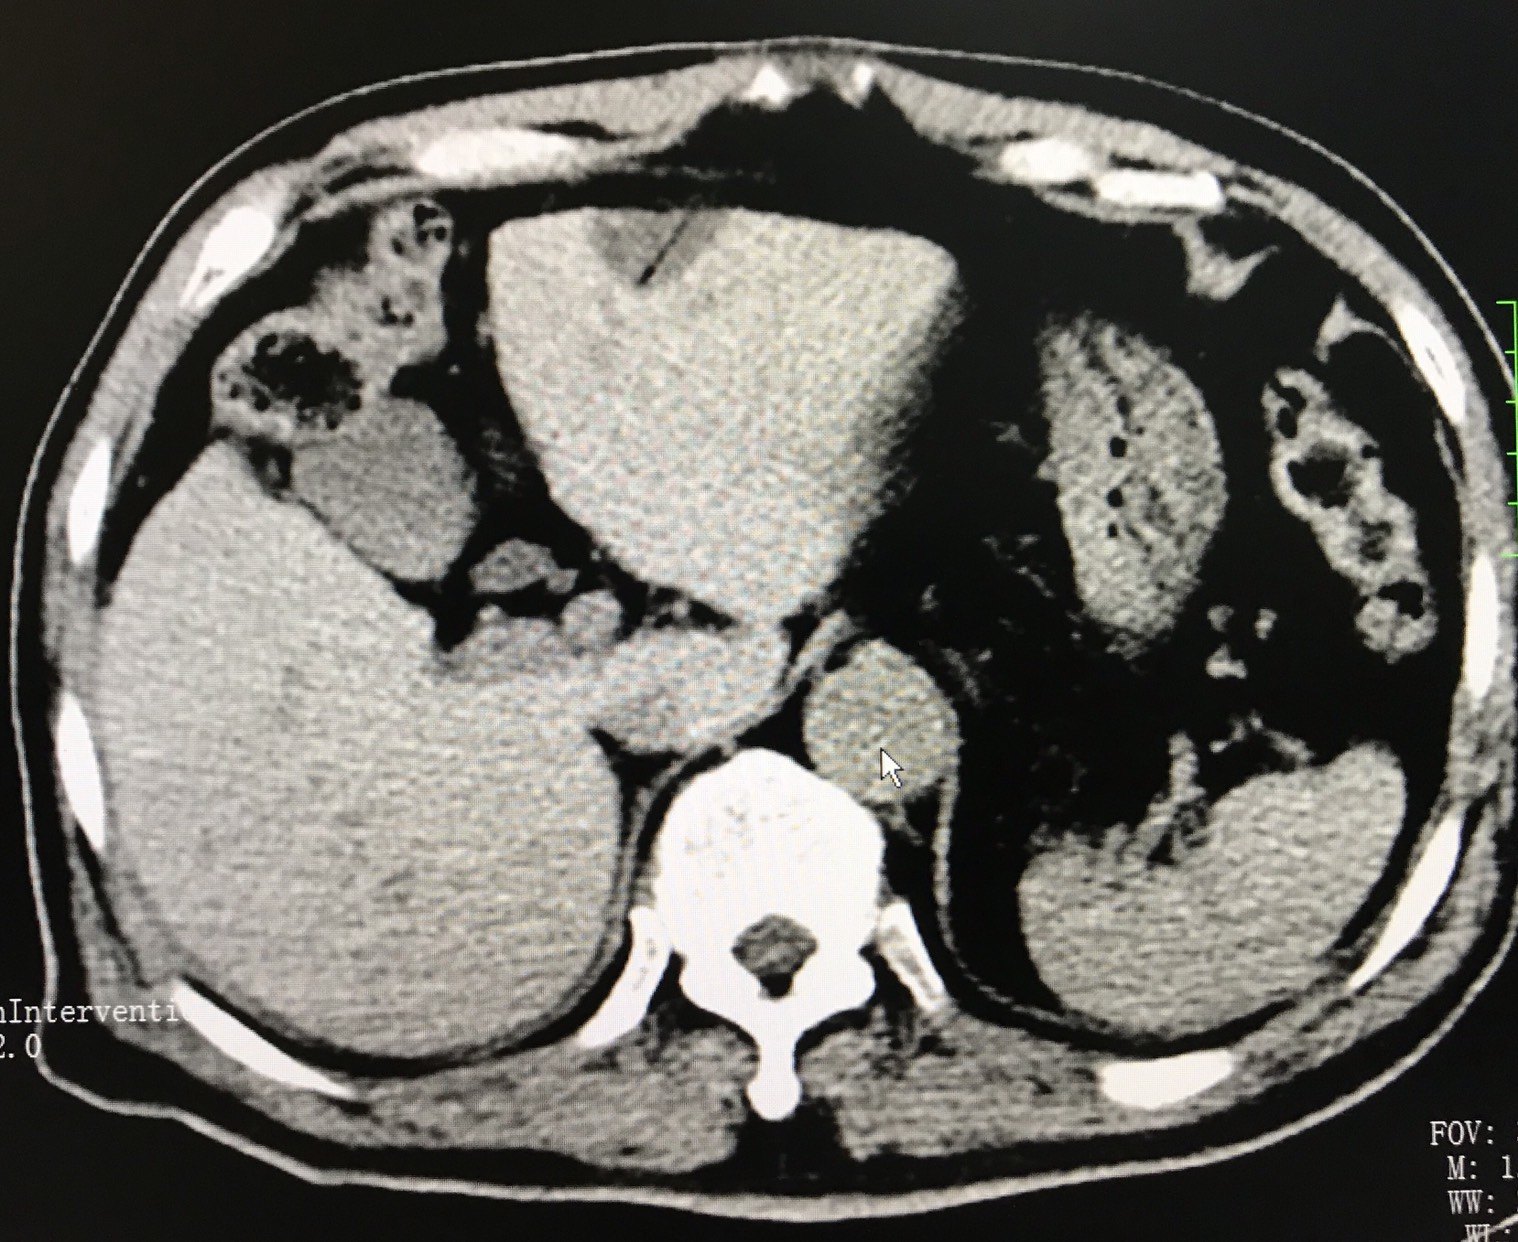

肝静脉癌栓的氩氦刀冷冻消融治疗案例分享

1590x1242 - 299KB - JPEG

1624x1242 - 480KB - JPEG

1292x1242 - 313KB - JPEG